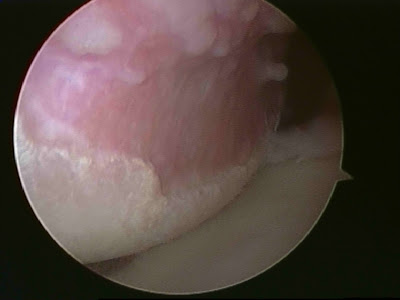

Picture showing completed Arthroscopic(key hole) repair.